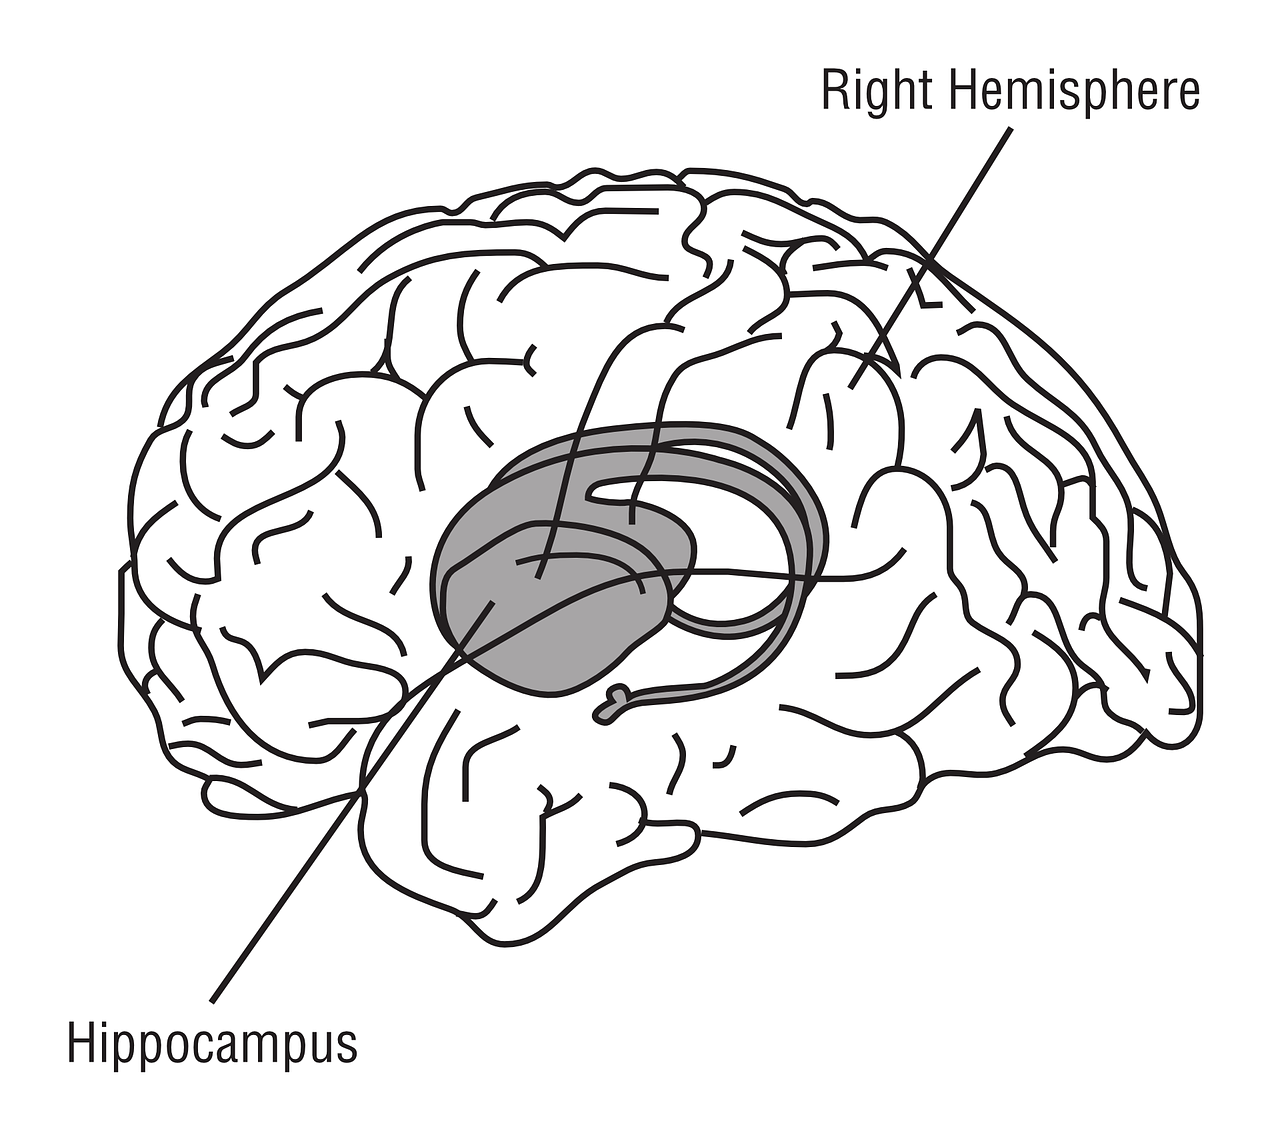

The hippocampus can be divided into three regions, the ventral, dorsal, and intermediate. The hippocampus is also found in the middle region of the temporal lobe but it has a seahorse shape that is different from that of the amygdala. Like the amygdala, it is part of the limbic system but it has a different shape and function. The similar location to the amygdala can lead to confusion of the hippocampus with the amygdala.

The amygdala occurs as two areas found in the middle part of the temporal lobes of the brain in front of the hippocampus. The hippocampus occurs as two areas found in the middle part of the temporal lobes behind the amygdala.

The amygdala is the shape of an almond. The hippocampus is the shape of a seahorse.

The three divisions of the amygdala are the centromedial nuclei, cortical-like nuclei, and basolateral nuclei. The three divisions of the hippocampus are ventral, dorsal, and intermediate regions.